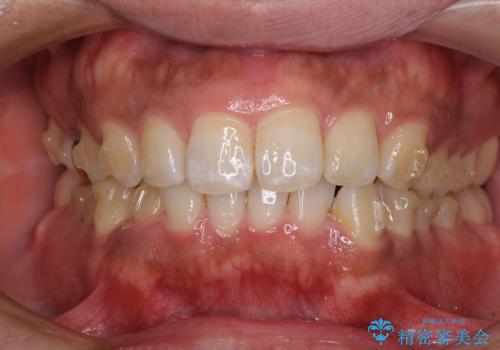

- 上下前歯部の叢生を気にして来院された患者様です。

レントゲン撮影により、右上奥歯が折れていることが分かりました。

患者様自身も何となく違和感を覚えていたとのことで、インプラント補綴治療を行うこととしました。

歯列不正は比較的軽微であったので、インビザラインによる矯正治療とし、矯正治療中にタイミングを見て抜歯とインプラント埋入を行う予定としました。